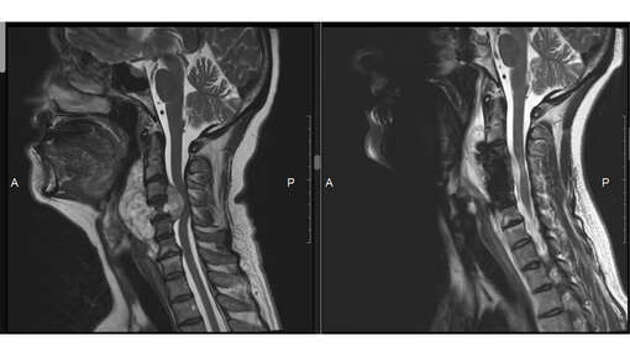

Хирурги Новосибирска прооперировали жительницу Алтайского края, у которой появилась опасная опухоль. Об этом сообщает Новосибирский научно-исследовательский институт травматологии и ортопедии им. Я.Л. Цивьяна. На проблемы со здоровьем женщина обратила внимание весной текущего года. Она часто жаловалась на головную боль, кисти и ноги иногда немели. Со временем ей стало тяжело глотать и говорить. "Мне было очень страшно, у меня даже руки не шевелились, руки и ноги были онемевшими. Сильно болела голова, приступы боли очень резко случались, и я спать не могла по ночам", – поделилась пациентка. Во время обследования у женщины обнаружили большую опухоль в шейном отделе позвоночника, которая разрушила один из шейных позвонков и сдавила спинной мозг. Женщине оперативно провели операцию. Специалисты удалили опухоль и стабилизировали работу позвоночника. Так как один из позвонков был разрушен, на его место установили имплантат. Несмотря на то, что для восстановления нужно время, женщина уже чувствует себя лучше.